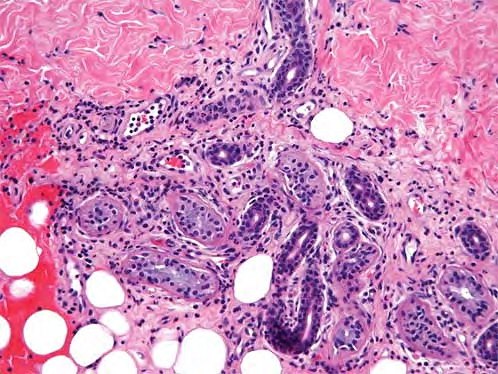

Idiopathic recurrent palmoplantar hidradenitis = التهاب الغدد العرقية الراحي الاخمصي الناكس ومجهول السبب